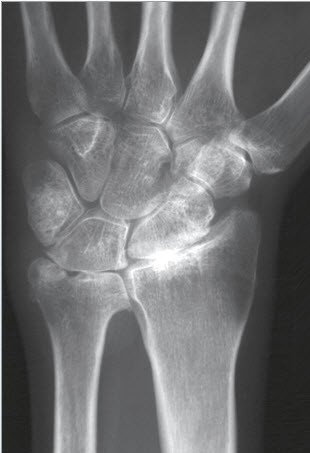

Eine Verdachtsdiagnose kann bereits durch die Patientenbefragung und das aktuelle Beschwerdebild gestellt werden. Gesichert wird die Diagnose einer Arthrose dann durch ein Röntgenbild. Findet sich nur eine leichte Arthrose, müssen möglicherweise Zusatzuntersuchungen durchgeführt werden. Bei fortgeschrittenen Arthrosen mit Gelenkzerstörung findet sich im Röntgenbild nur noch ein schmaler oder auch gänzlich fehlender Gelenkspalt (Abb. 1a bis 1c).